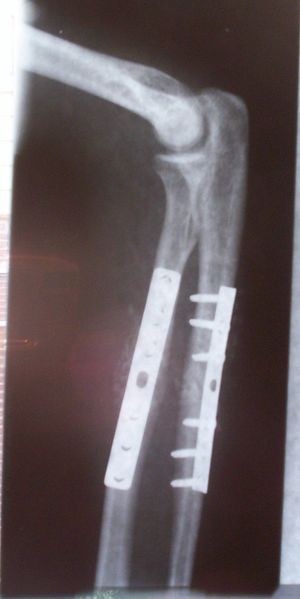

طب العظام يعنى بشكل عام بتصحيح الكسور جراحيا وتجبيرها إضافة إلى عمليات إصلاح وتبديل المفاصل التالفة. بالإضافة إلى أنواع أخرى من العمليات الجراحية التي تعالج أمراض العظام والجهاز الحركي.

جراحة العظام فرع من فروع الطب يعالج اعتلالات العظام والعضلات والأنسجة المتصلة بها. ويُدعى الأطباء الذين يُمارسون جراحة العظام جراحو العظام. وهم يُعالجون مُشكلات طبية كثيرة في هذا المجال منها الكسور، وإصابات الأوتار والأربطة، وتشوهات الأطراف والعمود الفقري. وقد توجد بعض الاعتلالات العظمية منذ الولادة، بينما تظهر اعتلالات أخرى أثناء الطفولة بسبب مشكلات تتعلق بالنمو، أو في فترة متأخرة من العمر نتيجة للشيخوخة. كما تحدث اعتلالات أخرى نتيجة إصابة ما أو مرض. ويُشكل المصابون في حوادث السيارات، أو الأنشطة الرياضية أو أثناء التنزه والاستجمام عددًا كبيرًا من المرضى الذين يعالجهم اختصاصيو العظام. ويصف الأطباء لمعالجة الاعتلالات العظمية الأدوية، والجراحة، والعلاج الطبيعي. وقد يقوم الاختصاصي، على سبيل المثال، بإجراء جراحة لتقويم كسر أو تشوه. وبعد الجراحة قد يستخدم الاختصاصي قالبًا أو مقبضًا، ويصف العلاج الطبيعي كي يساعد على الشفاء. مثل هذه المعالجة قد تشمل استخدام جهاز يطلق نبضات كهربائية تُساعد العظم على الالتئام. كما قد يقوم الاختصاصي بإجراء جراحة لاستبدال مفصل من البلاستيك أو المعدن أو من مواد أخرى بمفصل ملتهب، أو مصاب. والمفصل الذي يستبدل عادة أكثر من غيره، هو مفصل الورك.

- كسور العظام (Fractures)

- علاج كسور عظمتي الزند والكعبرة.

- إصلاح كسور أسفل عظمة الكعبرة.